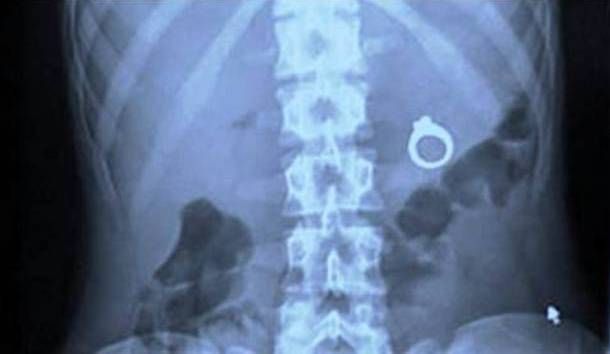

Some items are small enough that the body will expel them naturally, but others are large enough that they may cause intestinal blockage. An x-ray or CT scan may be required to determine the exact location and movement of the foreign body, which will help doctors determine whether they need to surgically remove the object.

If the item is small but potentially harmful, such as a button, battery or a magnet, doctors may decide to remove the foreign body before it causes damage.